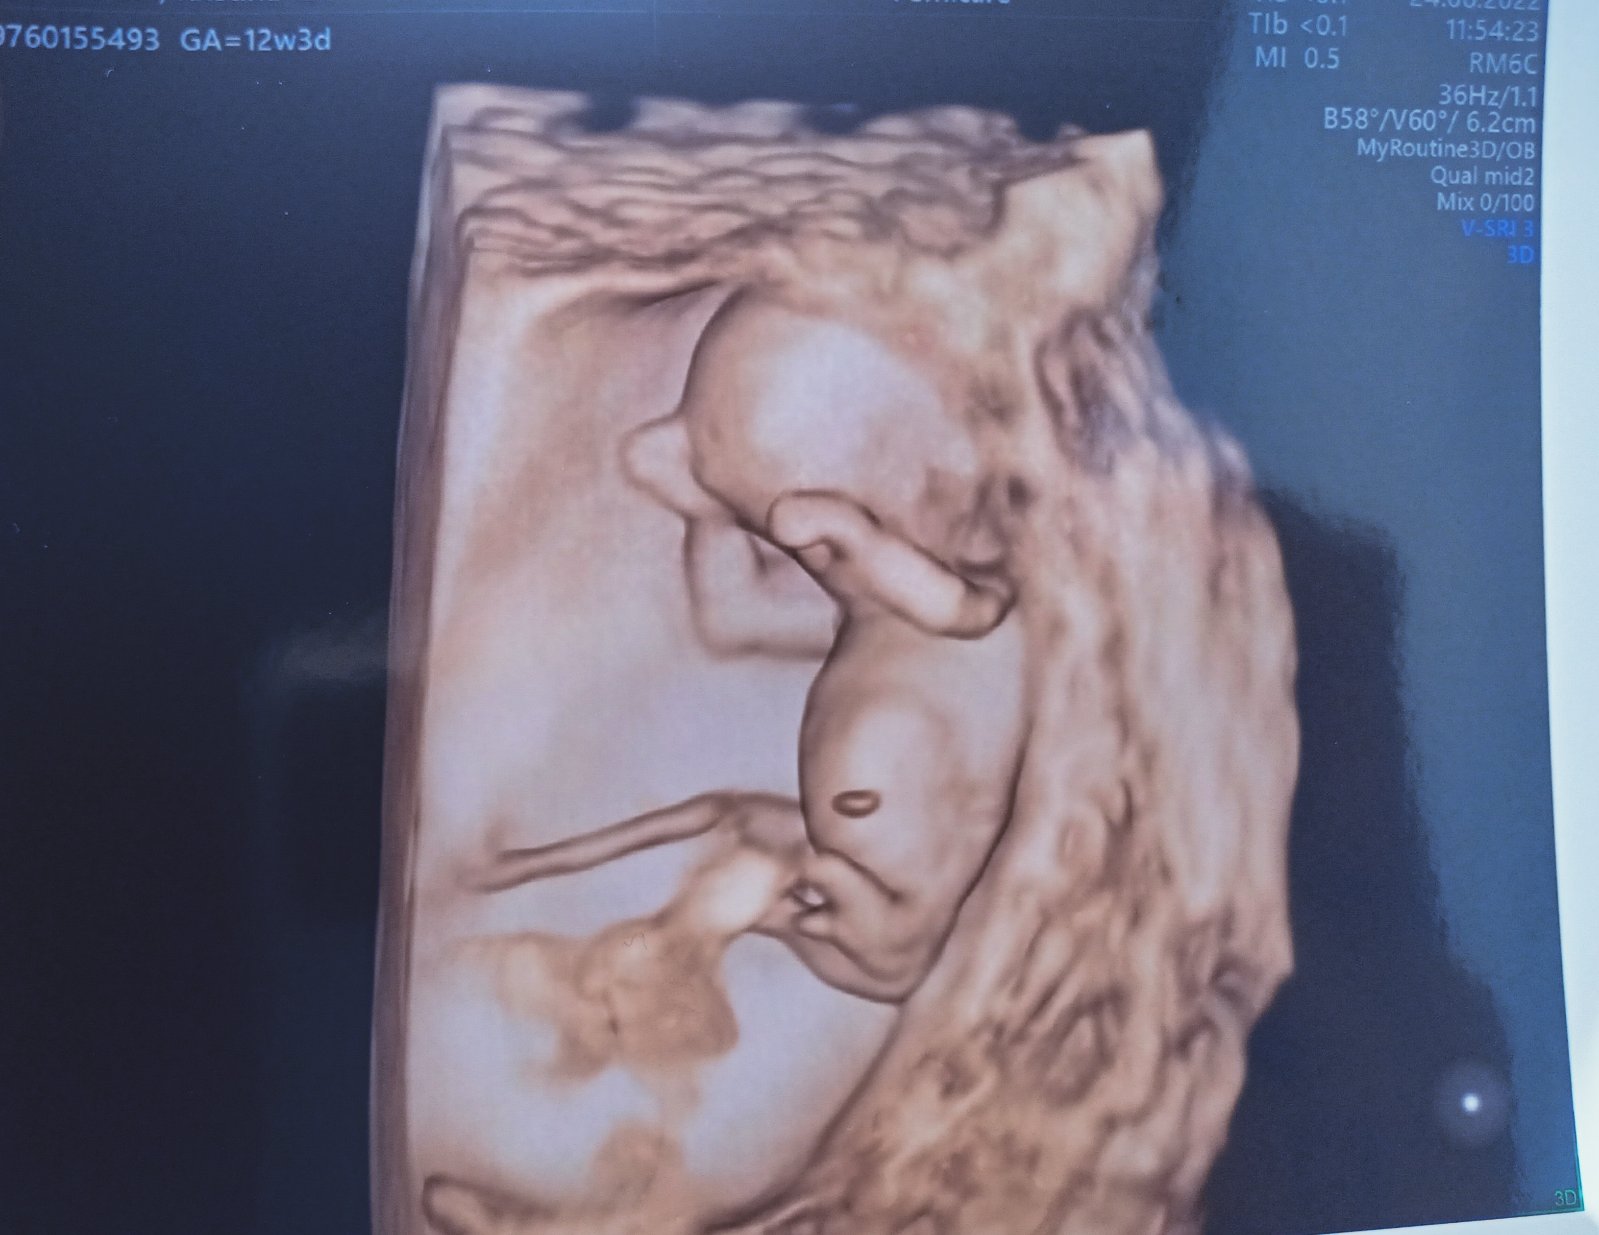

Aké je pohlavie dieťatka podľa tejto fotky?

Dobrý deň, pani doktorka,

vedeli by ste podľa tejto fotky určiť pohlavie?

Dobrý deň,

predpokladám, že chlapček. Ak je fotka schválne zrezaná pre zobrazenie pohlavia a nejde o artefakt.

MUDr. Tóthová N.

Gynekológ-pôrodník